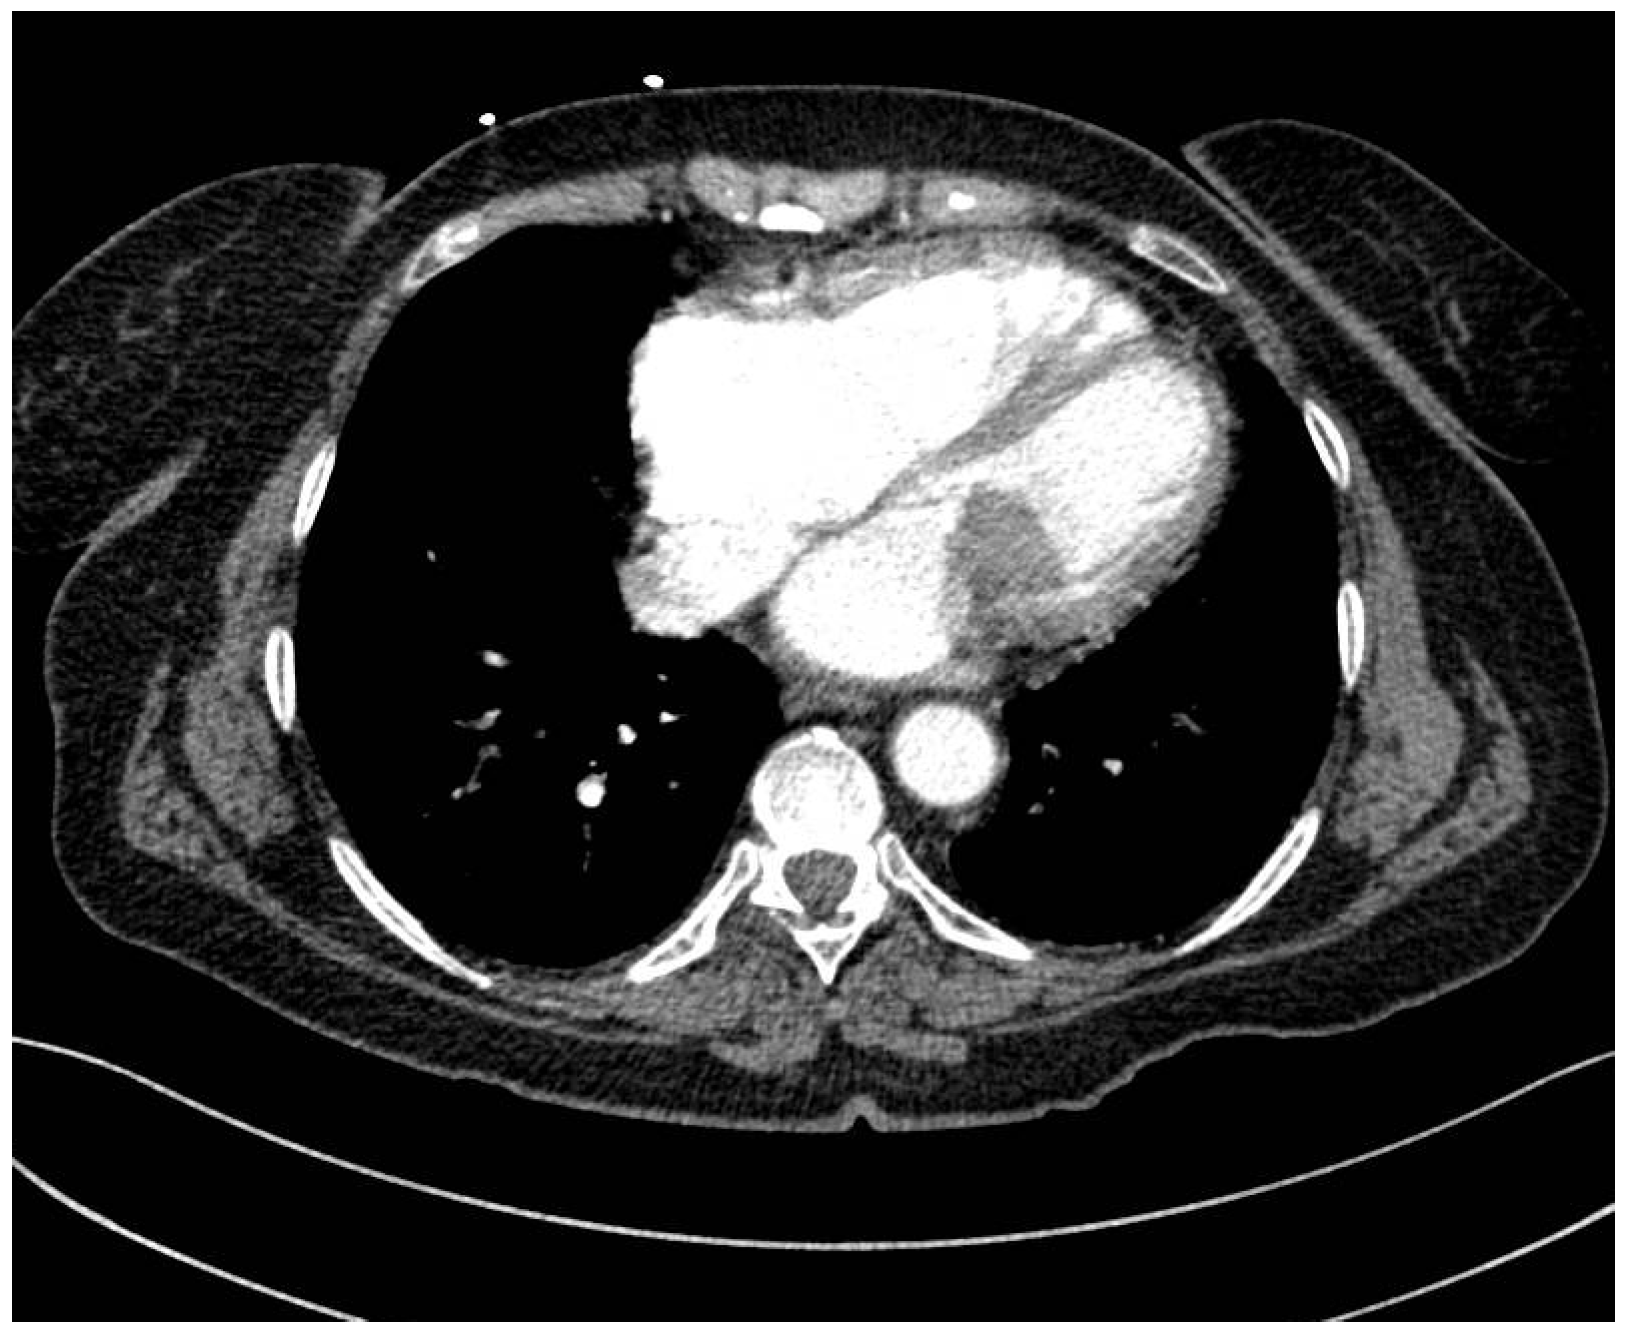

The patient experienced transitory neurological dysfunctions, and a confirmatory contrast CT was performed. Cranial CT showed a hyperdense left M2 with hypodense lesion with ischemic appearance (Figure 3). The thoracic CT scan showed a 3.6 × 2.6 cm hypodense nodule at the center of mitral valve, with extension toward the aortic valve (Figure 4). Furthermore, a new occlusion in the left internal carotid artery was observed due to a thrombus (at least 5 cm) starting from its emergence from the aorta (Figure 5). Pulmonary arteries were permeable. We used a GE Healthcare Japan Corporation, Tokyo, Japan, model Optima CT660, year of fabrication 2015 to perform the emergency scan.

Figure 4. CT images of the thorax axial section with 3.6/2.6 cm hypodense nodule at the center of the mitral valve.